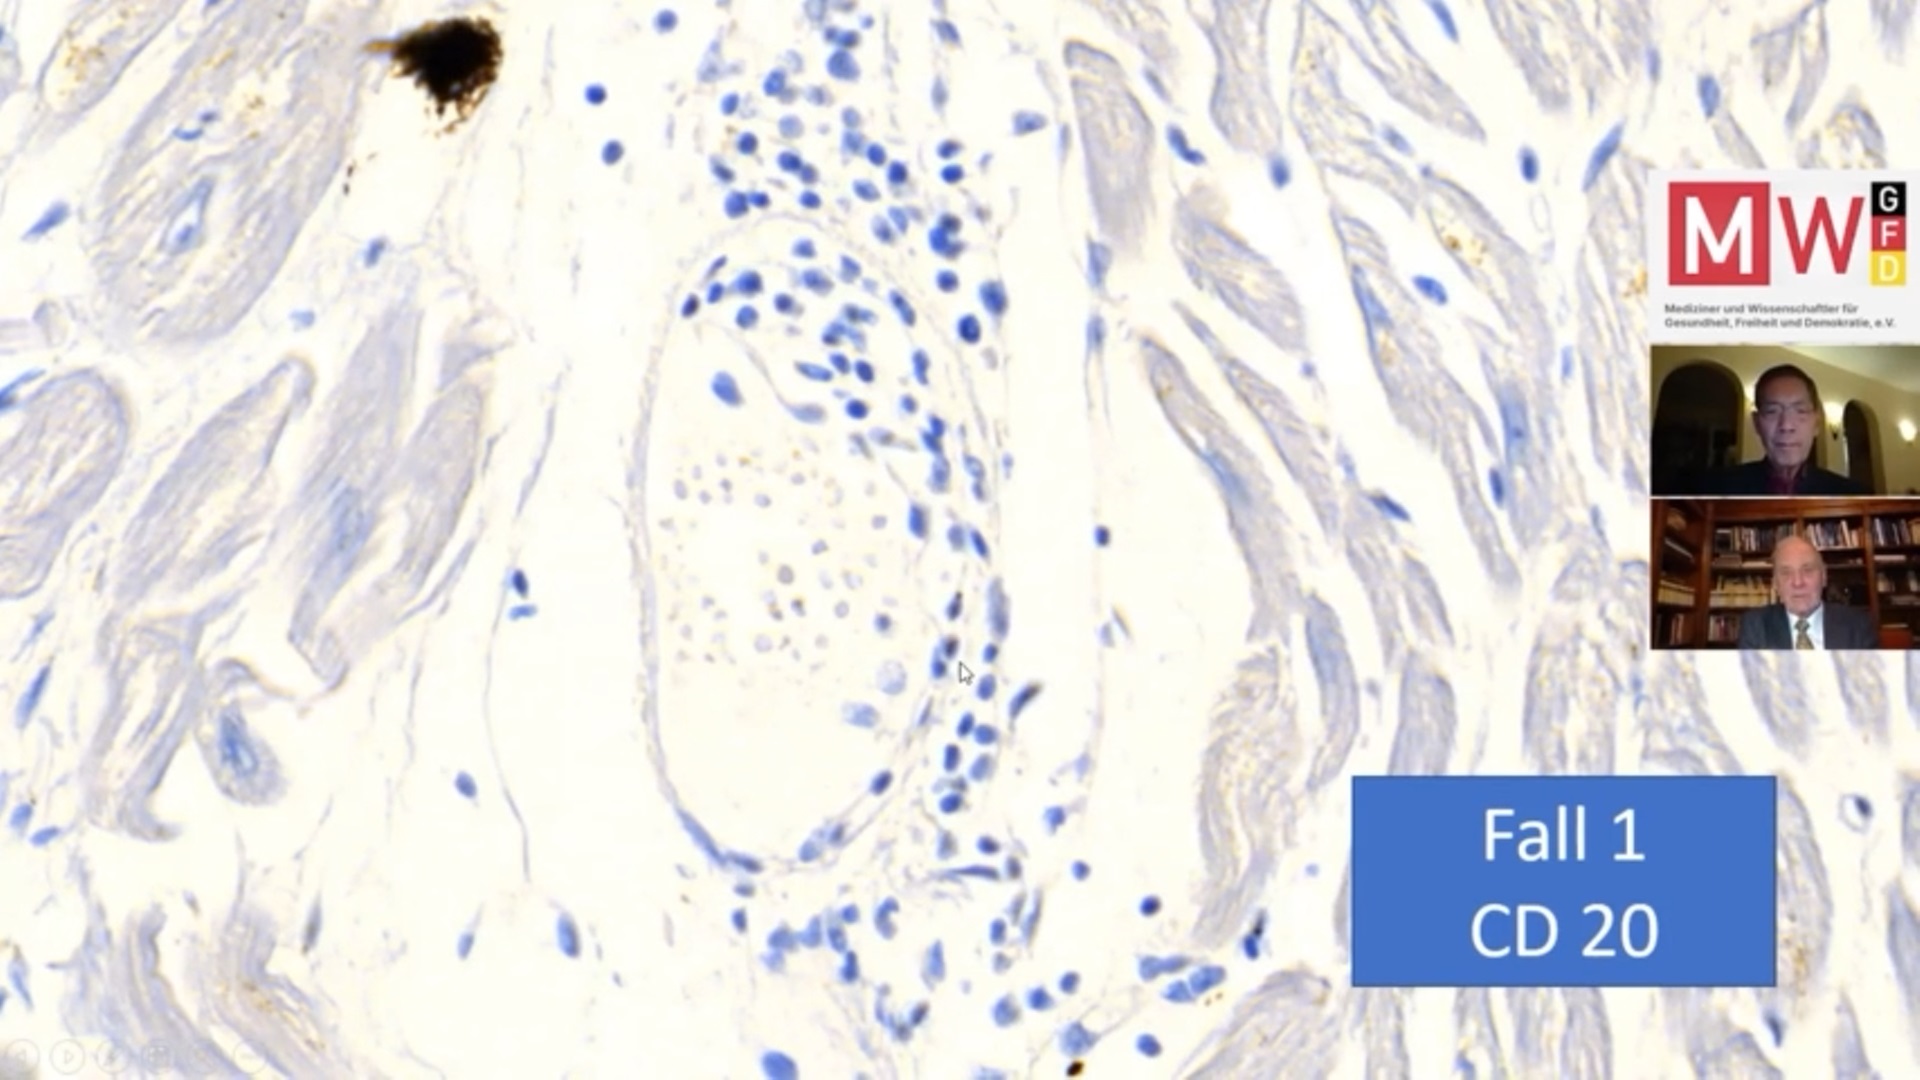

Η πρώτη διαφάνεια που έδειξε είναι από επιπλοκές που δημιουργήθηκαν στην καρδιά:

Στην τρίτη διαφάνεια στέκεται στα μπλε στίγματα, τονίζοντας ότι τα λεμφοκύτταρα δείχνουν να κάνουν επίθεση στην καρδιά.